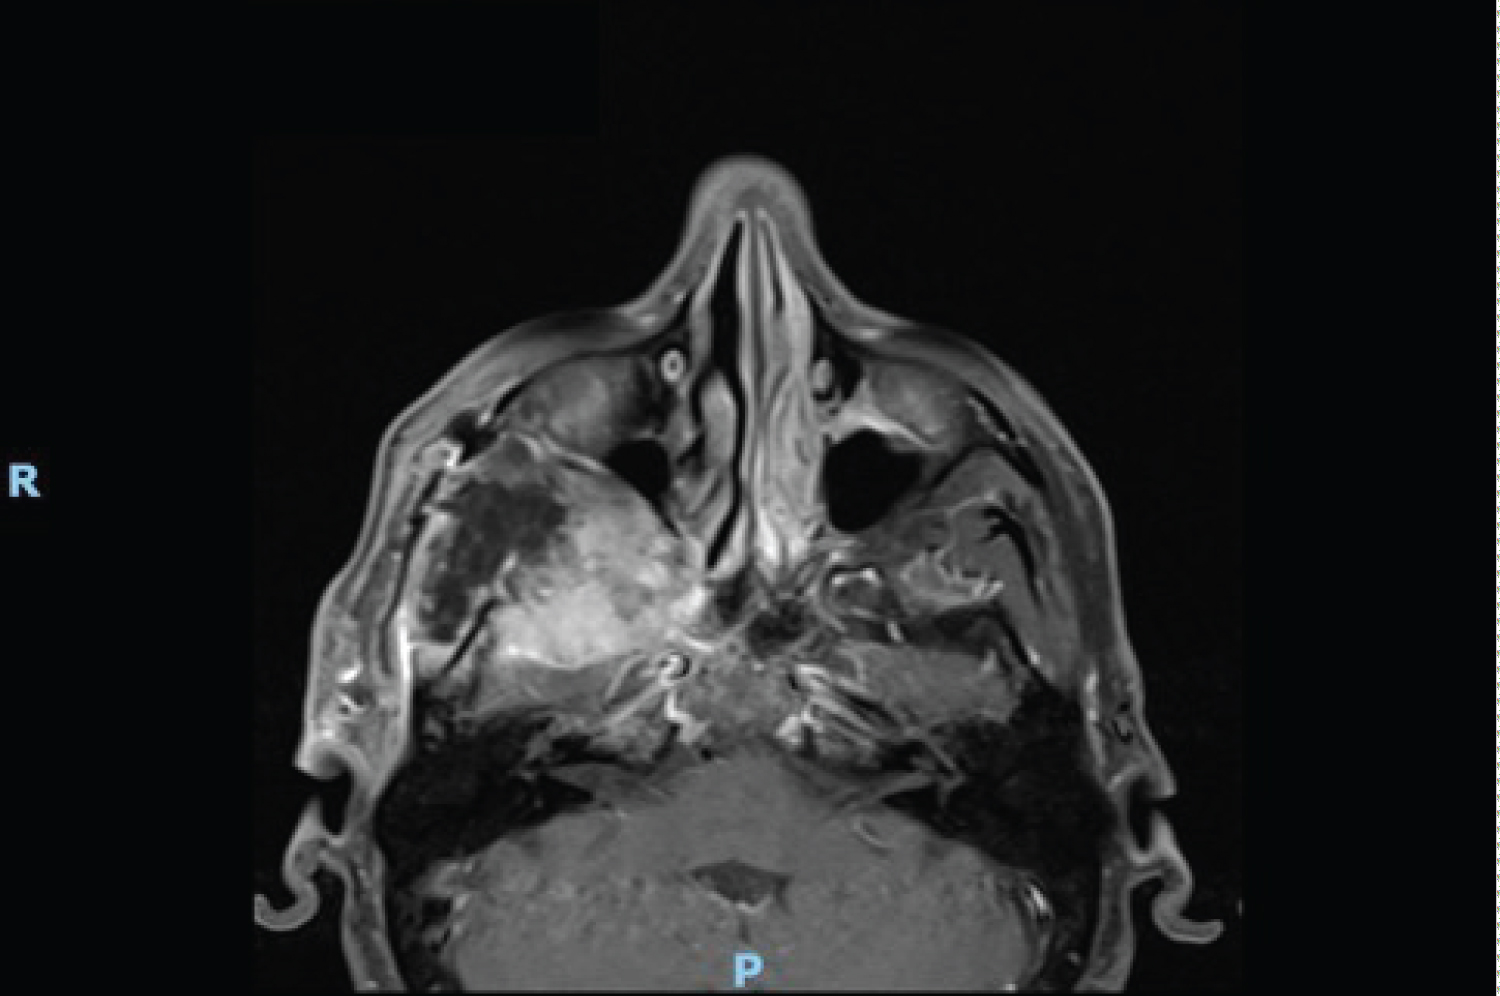

A contrast computer tomography (CT) and a Magnetic resonance imaging (MRI) were performed and revealed a 70 × 28 mm extra-axial neoplasm in the right temporal fossa up to the inferior orbital fissure. This mass came in touch with the extrinsic eye muscles causing perilesional oedema. The right temporal lobe, the right masseter and the right temporal muscle were compressed by the lesion, while the right temporal bone was eroded (Figure 1, Figure 2, Figure 3 and Figure 4).

Figure 3: MRI pre-operative axial T1 image. View Figure 3